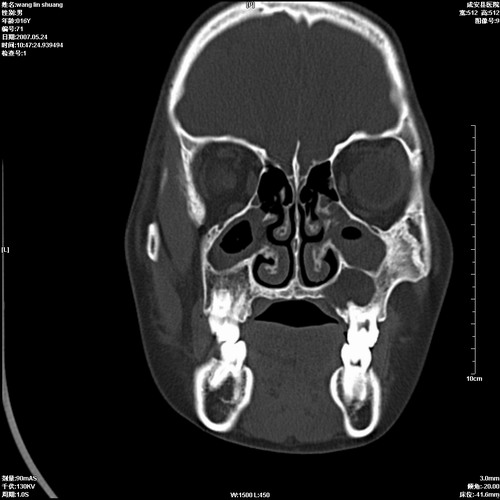

病人,男 16岁,鼻旁右肿胀,其余无不适感,ct图片

1、典型右侧根尖囊肿。

2、双侧上颌窦、筛窦、蝶窦炎

1\\左侧上颌骨含牙囊肿

2\\两上颌窦炎

右侧上颌骨含牙囊肿.双侧上颌窦炎症.

右侧上颌骨含牙囊肿.双侧上颌窦、蝶窦右侧炎症.

1、左侧上颌骨含牙囊肿。

典型的右侧上颌骨含牙囊肿,双侧上颌窦、右侧蝶窦炎症。

右侧上颌骨含牙囊肿,全组鼻窦炎